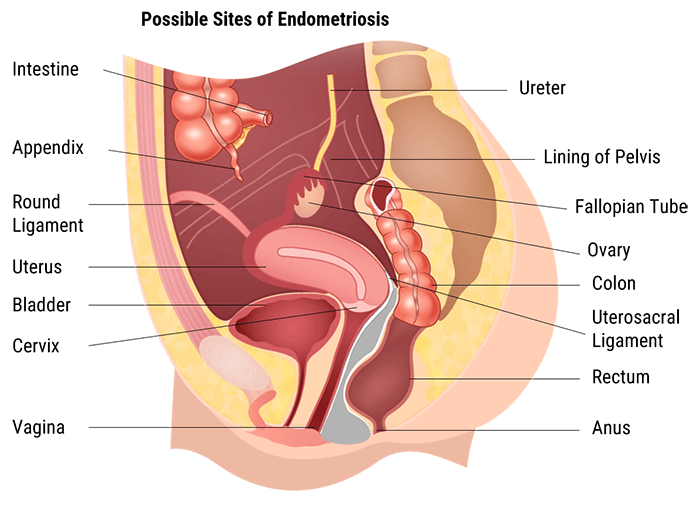

The pelvic cavity is a body cavity that is bounded by the bones of the pelvis. It contains primarily the reproductive organs, the urinary bladder, the pelvic colon, and the rectum. In the female, the uterus and vagina occupy the interval between these viscera.

Each radiographer shall obtain a relevant medical history from a patient regarding the area that requires imaging before starting the exam. The information must be decoded and then sent correctly to the radiologist. Patients often refer to any region of their abdominopelvic cavity as their “stomach”. However, it is possible to determine the quadrant or the region of interest by asking the patient to point to the area of interest.

In this section we will explain how the abdominopelvic cavity is divided into 4 quadrants or 9 regions.